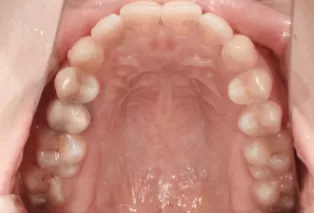

Intraoral photos